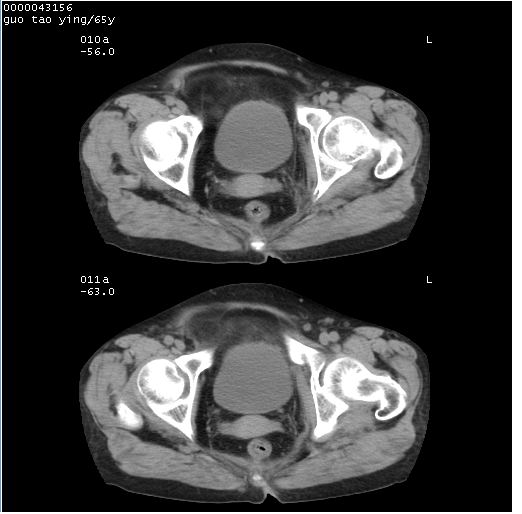

以下是引用黑白光影在2008-1-30 13:22:00的发言:[br]支持左耻骨骨折。[br]未见骶骨骨质明确破坏改变。[br]经楼主提示(勿局限于外伤)。考虑为右侧腹股沟直疝。[br][br][br][br]